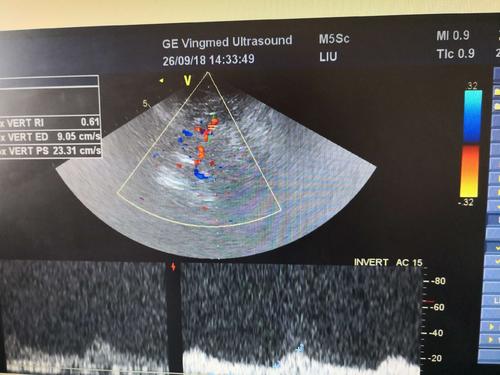

經(jīng)顱彩色編碼雙功能超聲,區(qū)別于經(jīng)顱多普勒超聲,它的英文簡稱是TCCD,后者是TCD。TCCD成像模式是什么樣的,tcd廠家澳思泰今天來分析這一問題。

(1)依據(jù)多普勒頻移值編碼成像即f-TCCD:

依賴運(yùn)動(dòng)紅細(xì)胞所產(chǎn)生的多普勒頻移值進(jìn)行計(jì)算機(jī)編碼,可以顯示血流方向和測算血流速度,需要校正多普勒取樣角度,角度及篩查深度依賴性較大,較易產(chǎn)生運(yùn)動(dòng)偽像。

(2)依據(jù)運(yùn)動(dòng)紅細(xì)胞所產(chǎn)生的總能量進(jìn)行編碼成像即p-TCCD:

只與運(yùn)動(dòng)紅細(xì)胞所產(chǎn)生的總能量有關(guān),無需校正多普勒取樣角度,對(duì)于受取樣角度影響較大血管病變,諸如大腦后動(dòng)脈(PCA),大腦中動(dòng)脈(MCA)M2段,大腦前動(dòng)脈(ACA)A1段有一定的幫助作用,信噪比更高,不易產(chǎn)生混疊效應(yīng)。p-TCCD相對(duì)f-TCCD而言,缺點(diǎn)是不能顯示血流方向,對(duì)顯示狹窄處高速血流敏感性較低。